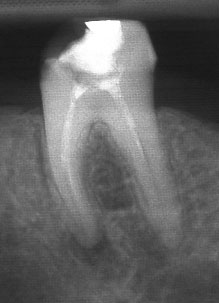

При добре проведено ендодонтско лечение кореновият канал е запълнен точно до стеснението, разположено на 1 - 1.5 мм. от края на канала - т.нар. физиологично стеснение. Не бива да остава незапълнена част от канала. Много често се получава припресване на канлопълнежното средство извън канал на зъба, в тъканите около корена.

Рентгенографии на добре пролекувани зъби